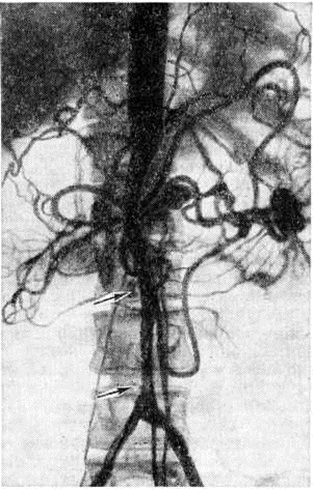

Топическую картину поражения можно установить пробой изотопной и рентгеноконтрастной ангиографии. Изотопная ангиография (смотри полный свод знаний) осуществляется пробой внутривенного введения технеция 99-м. Из методов рентгеноконтрастного исследования предпочтение следует отдать транслюмбальной пункционной аортографии (смотри полный свод знаний), при которой возможно получить изображение не только аорты, но и дистального сосудистого русла конечностей. Именно аортография выявляет локализацию и протяжённость поражения (рисунок 4—6), однако её следует проводить только при решении вопроса об оперативном лечении больного.

Рис. 4.

Аортограмма больного с синдромом Лериша при атеросклеротическом поражении бифуркации аорты и общих подвздошных артерий: окклюзия правой общей подвздошной артерии; стенозы левой подвздошной артерии указаны стрелками.